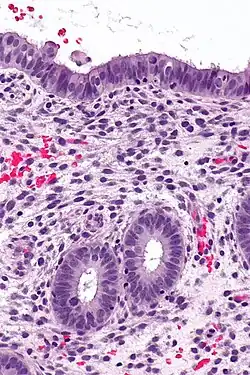

![]() | Endometrium | Micrograph showing proliferative phase of endometrium. | Category: Histology of endometrium | endometrium |